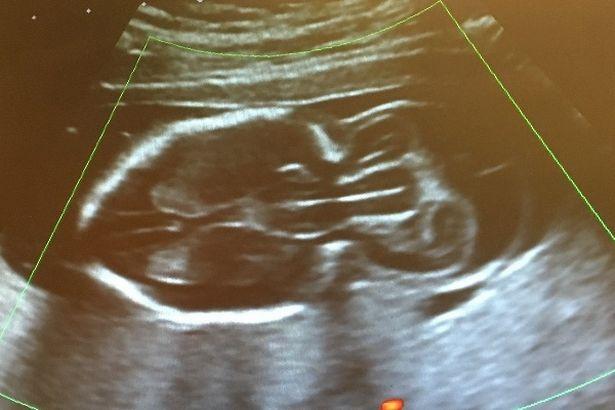

Ngay từ khi chào đời, May mắc chứng thoát vị não (Encephalocele) - một dạng dị tật bẩm sinh rất hiếm gặp, khiến cho phần não của tràn qua vết nứt của hộp sọ phía sau đầu và hình thành một bướu lớn ở đó.

Bác sĩ đã chẩn đoán May Rose Gibney mắc chứng bệnh hiếm từ tuần thai thứ 20